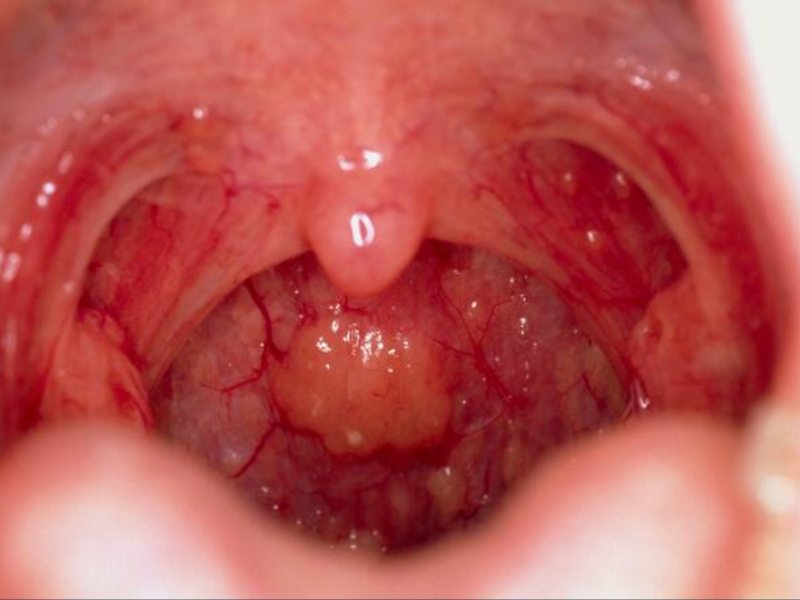

سرطان حنجره یکی از انواع سرطانهایی است که در ناحیه گلو و تارهای صوتی شکل میگیرد...

- ۲۰ جولای ۲۰۲۵